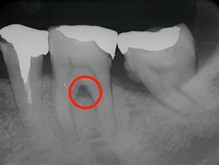

歯周病が進行して、歯の根元まで炎症が広がることがあります。右の写真をご覧ください。赤丸で囲んだ分が黒くなっています。ここは、歯肉が衰え、歯と歯肉の間にできたすき間です。ここに付着した歯石を取り除くことはできません。放置すると歯周病がさらに進行して、やがて抜歯となってしまうでしょう。

そこで、外科的手術で歯の根を露出させて歯石を取り除きます。さらに歯の根の間に歯間ブラシが入るように穴をあけ、お手入れしやすくします。この術式を「トンネリング」といいます。